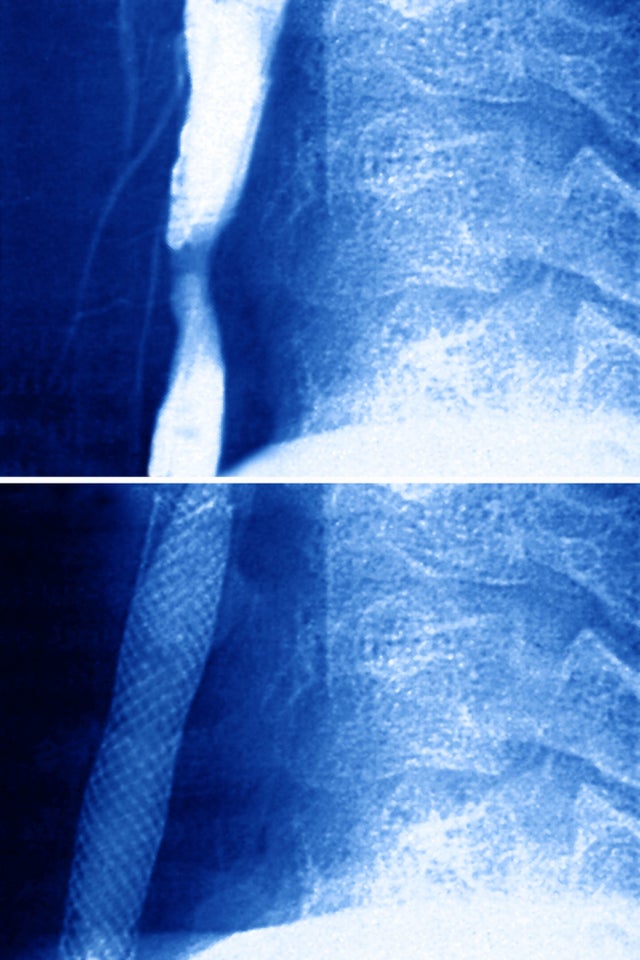

22. Spinal fusion

Spinal fusions cost an average of $67,826, before insurance.

16. Laminectomy

During a laminectomy, doctors remove the rear section of bone from one or more vertebrae. This procedure costs an average of $73,363, before insurance.

14. Lumbar spine surgery

Hospitals charge an average of $75,361 for surgery on the lower section of the spine.